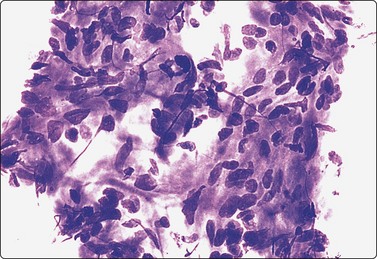

image image

Fig. 7.15 Regenerative epithelial atypia in mastitis

(A) Atypical, reactive/regenerating epithelial cells with a background of histiocytes, inflammatory cells and debris (MGG, HP); (B) Corresponding tissue section (H&E, IP).